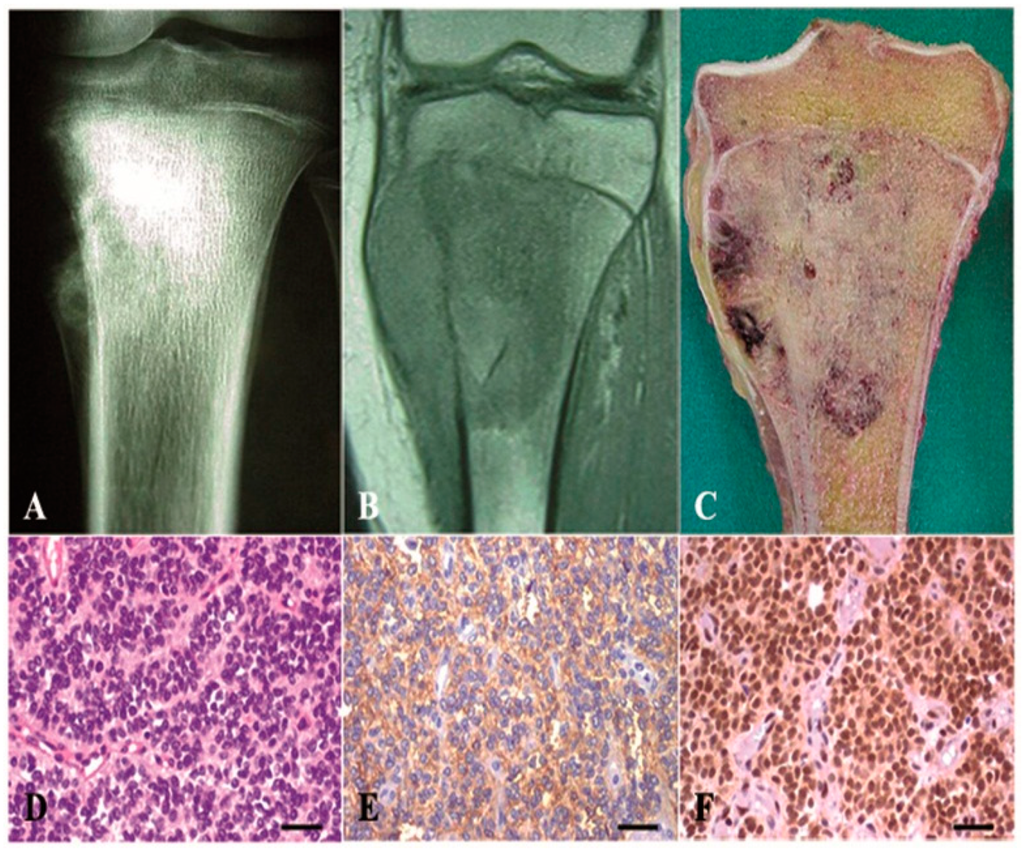

| Patient | Age | Gender | Primary Site | HBA71 | CD99 | CD45 | VIM | NSE | NF | CAM 5.2 | Myogenin | FLI-1 | Pattern |

|---|---|---|---|---|---|---|---|---|---|---|---|---|---|

| 1 | 16 | M | Femur | + | + | − | + | + | − | − | − | + | Diffuse |

| 2 | 40 | M | Foot | + | + | − | + | +/− | − | − | − | + | Diffuse, filigree |

| 3 | 28 | F | Bone pelvis | + | + | − | + | − | − | − | − | + | Diffuse, filigree |

| 4 | 19 | M | Bone pelvis | + | + | − | + | + | + | − | − | + | Diffuse |

| 5 | 15 | M | Arm | + | + | − | + | − | − | − | − | + | Diffuse, pseudorosettes |

| 6 | 40 | M | Arm | + | + | − | + | + | + | − | − | + | Diffuse, filigree |

| 7 | 14 | M | Humerus | + | + | − | + | +/− | − | − | − | + | Diffuse |

| 8 | 24 | M | Scapula | + | + | − | + | +/− | +/− | − | − | + | Diffuse, pseudorosettes |

| 9 | 30 | M | Humerus | + | + | − | + | + | + | + | − | + | Large cells |

| 10 | 30 | M | Bone pelvis | + | + | − | + | + | − | − | − | + | Diffuse, filigree |

| 11 | 38 | M | Femur | + | + | − | + | − | − | − | − | + | Diffuse, large cells |

| 12 | 12 | F | Bone pelvis | + | + | − | + | + | − | − | − | + | Diffuse |

| 13 | 26 | M | Femur | + | + | − | + | + | − | − | − | + | Diffuse, filigree |

| 14 | 18 | M | Rib | + | + | − | + | + | − | − | − | + | Diffuse |

| 15 | 5 | F | Bone pelvis | + | + | − | + | + | − | − | − | + | Filigree |

| 16 | 15 | F | Sacrum | + | + | − | + | +/− | − | − | − | + | Diffuse, pseudorosettes |

| 17 | 9 | M | Humerus | + | + | − | + | − | − | − | − | + | Diffuse |

| 18 | 30 | F | Bone pelvis | + | + | − | + | − | +/− | − | − | + | Diffuse |

| 19 | 38 | M | Tibia | + | + | − | + | − | − | − | − | ± | Diffuse |

| 20 | 16 | F | Iliac wing | + | + | − | + | +/− | − | − | − | + | Diffuse, pseudorosettes |